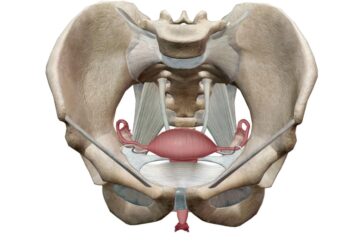

Osteoartritas – tai dažniausiai pasitaikantis sąnarių sutrikimas, kurį nulemia laipsniškas sąnarių kremzlės nusidėvėjimas. Šios ligos metu kremzlė, paprastai apsauganti sąnarinius...